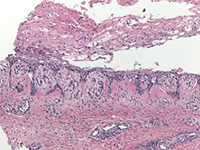

アフリカ系アメリカ人女児、12歳。1年ほど前から体幹、臀部、下肢にそう痒を伴う脱色素斑が出現した。リンパ節腫大はない。これまで皮膚軟化薬とトリアムシノロン0.1%クリーム1日2回外用などの治療を行ってきたという。皮膚生検では…